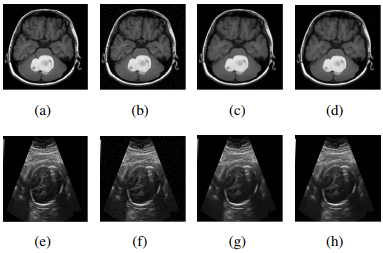

• This paper proposes a model that eliminates combined additive and multiplicative noise by merging the Rudin, Osher, and Fatemi (ROF) and I-divergence data fidelity terms. Many important techniques for denoising and restoring medical images were included in this model. The addition of the I-divergence fidelity term increases the complexity of the model and difficulty of the solution in comparison with the ROF. To solve this model, we first proposed the generalized concept of the maximum common factor based on the inverse scale space algorithm. Different from general denoising algorithms, the inverse scale space method exploits the fact that $ u $ starts at some value $ c_0 $ and gradually approaches the noisy image $ f $ as time passes which better handles noise while preserving image details, resulting in sharper and more natural-looking images. Furthermore, a proof for the existence and uniqueness of the minimum solution of the model was provided. The experimental findings reveal that our proposed model has an excellent denoising effect on images destroyed by additive noise and multiplicative noise at the same time. Compared with general methods, numerical results demonstrate that the nonlinear inverse scale space method has better performance and faster running time on medical images especially including lesion images, with combined noises.